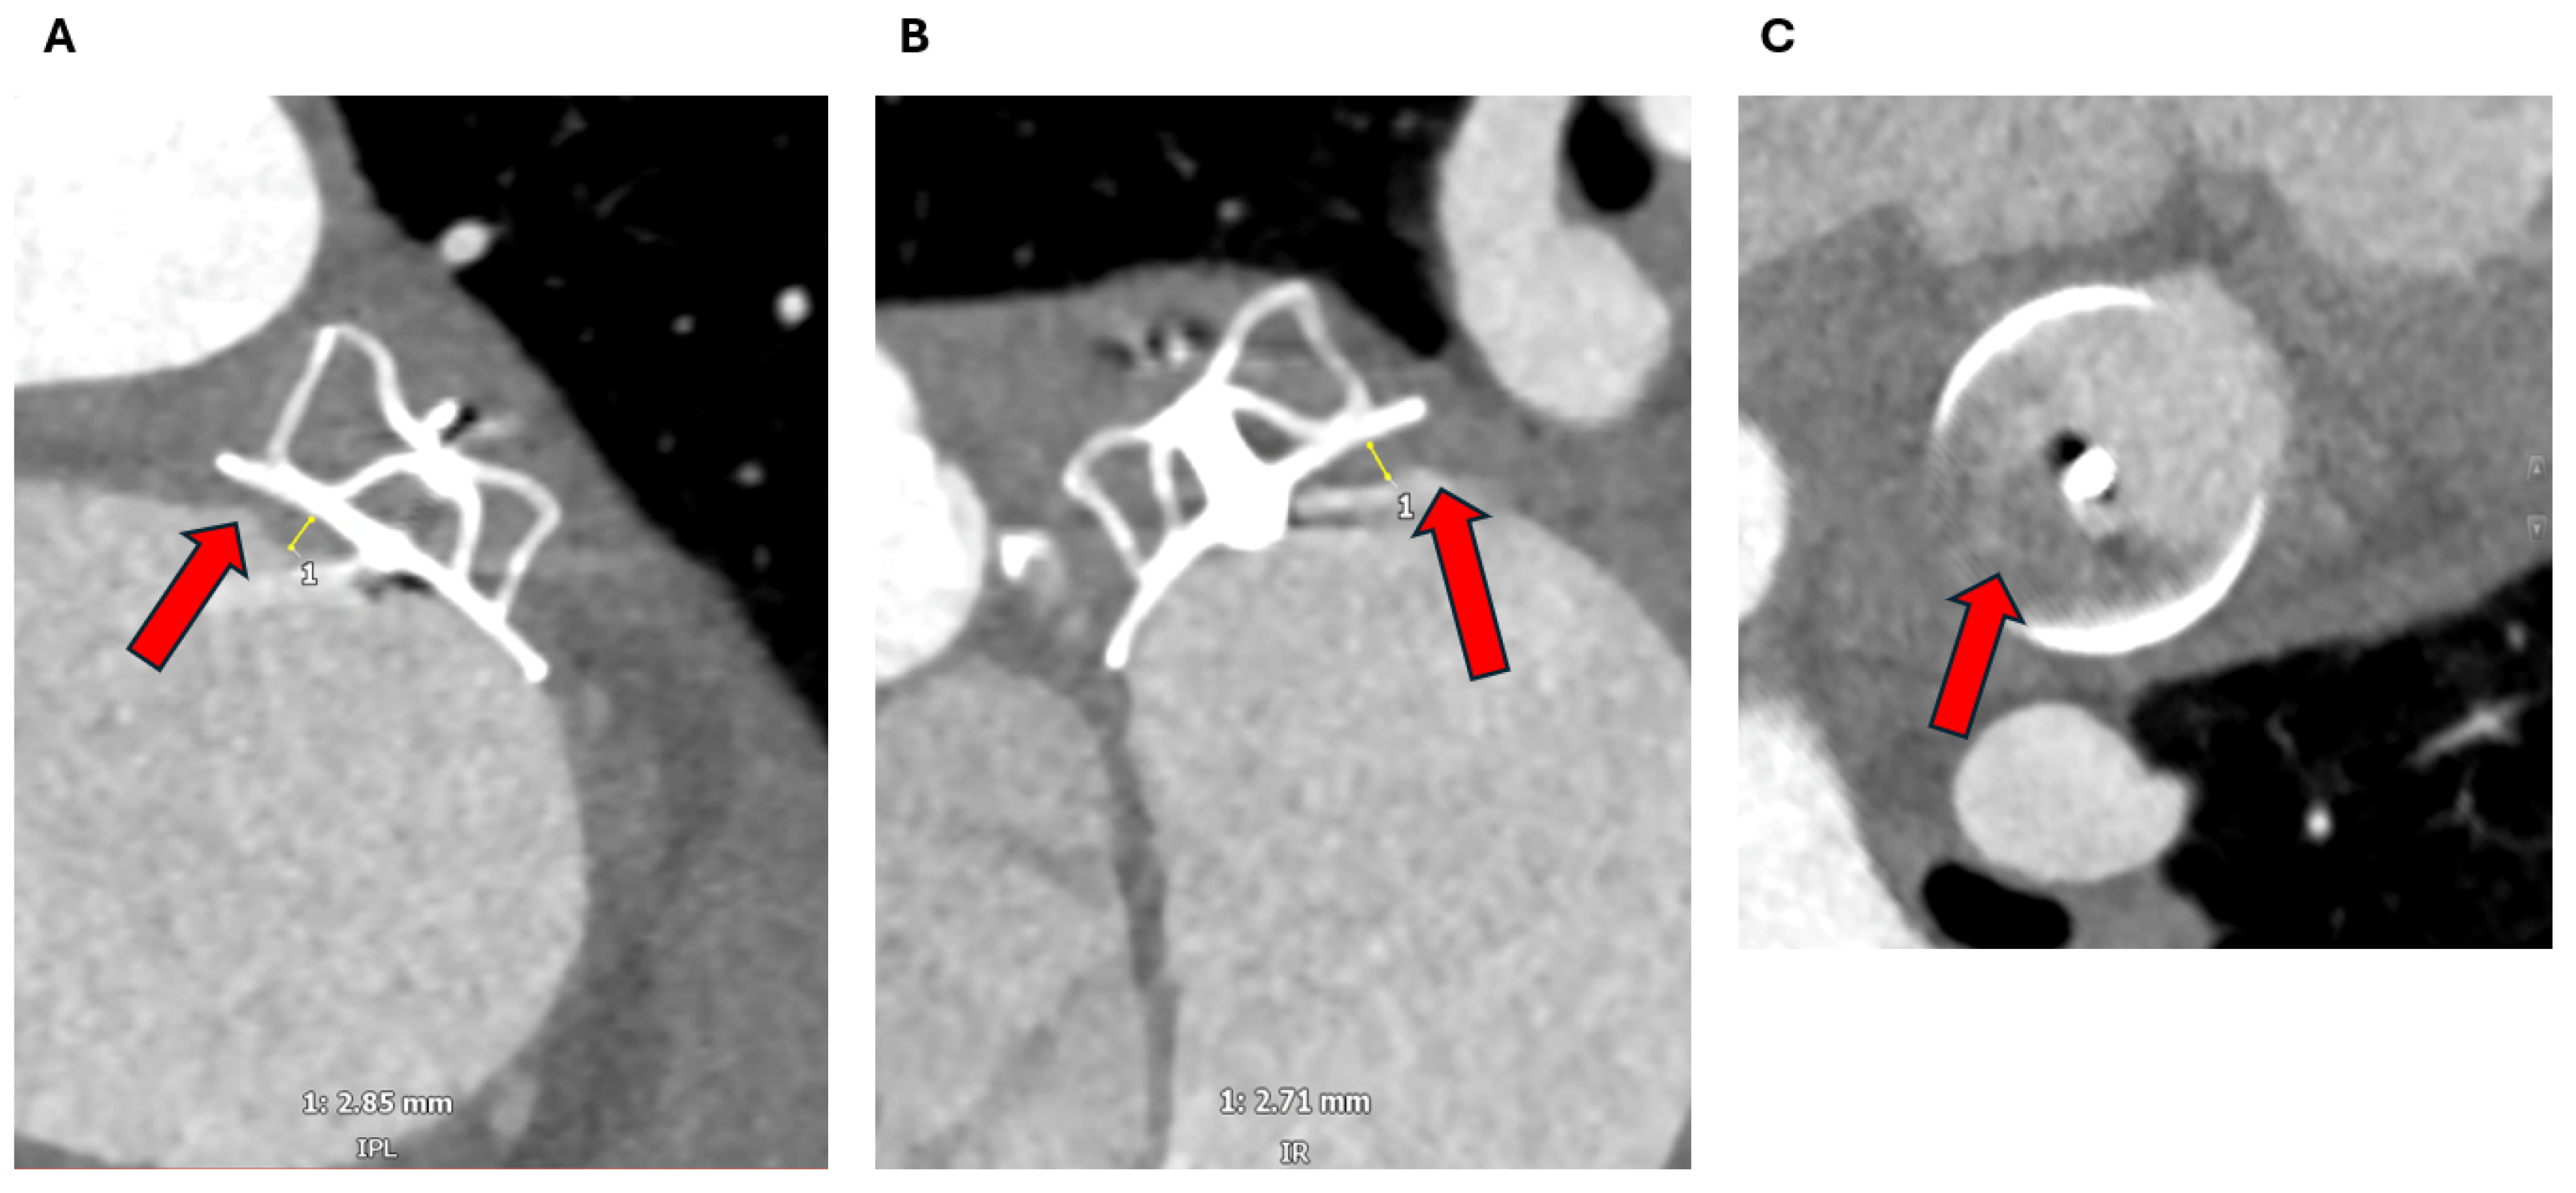

2.1.3. Assessment of the Inter-Atrial Septum

3.1. Device Position and Embolization

3.2. Peri-Device Leaks

3.3. Device-Related Thrombus

3.5. Epicardial Devices